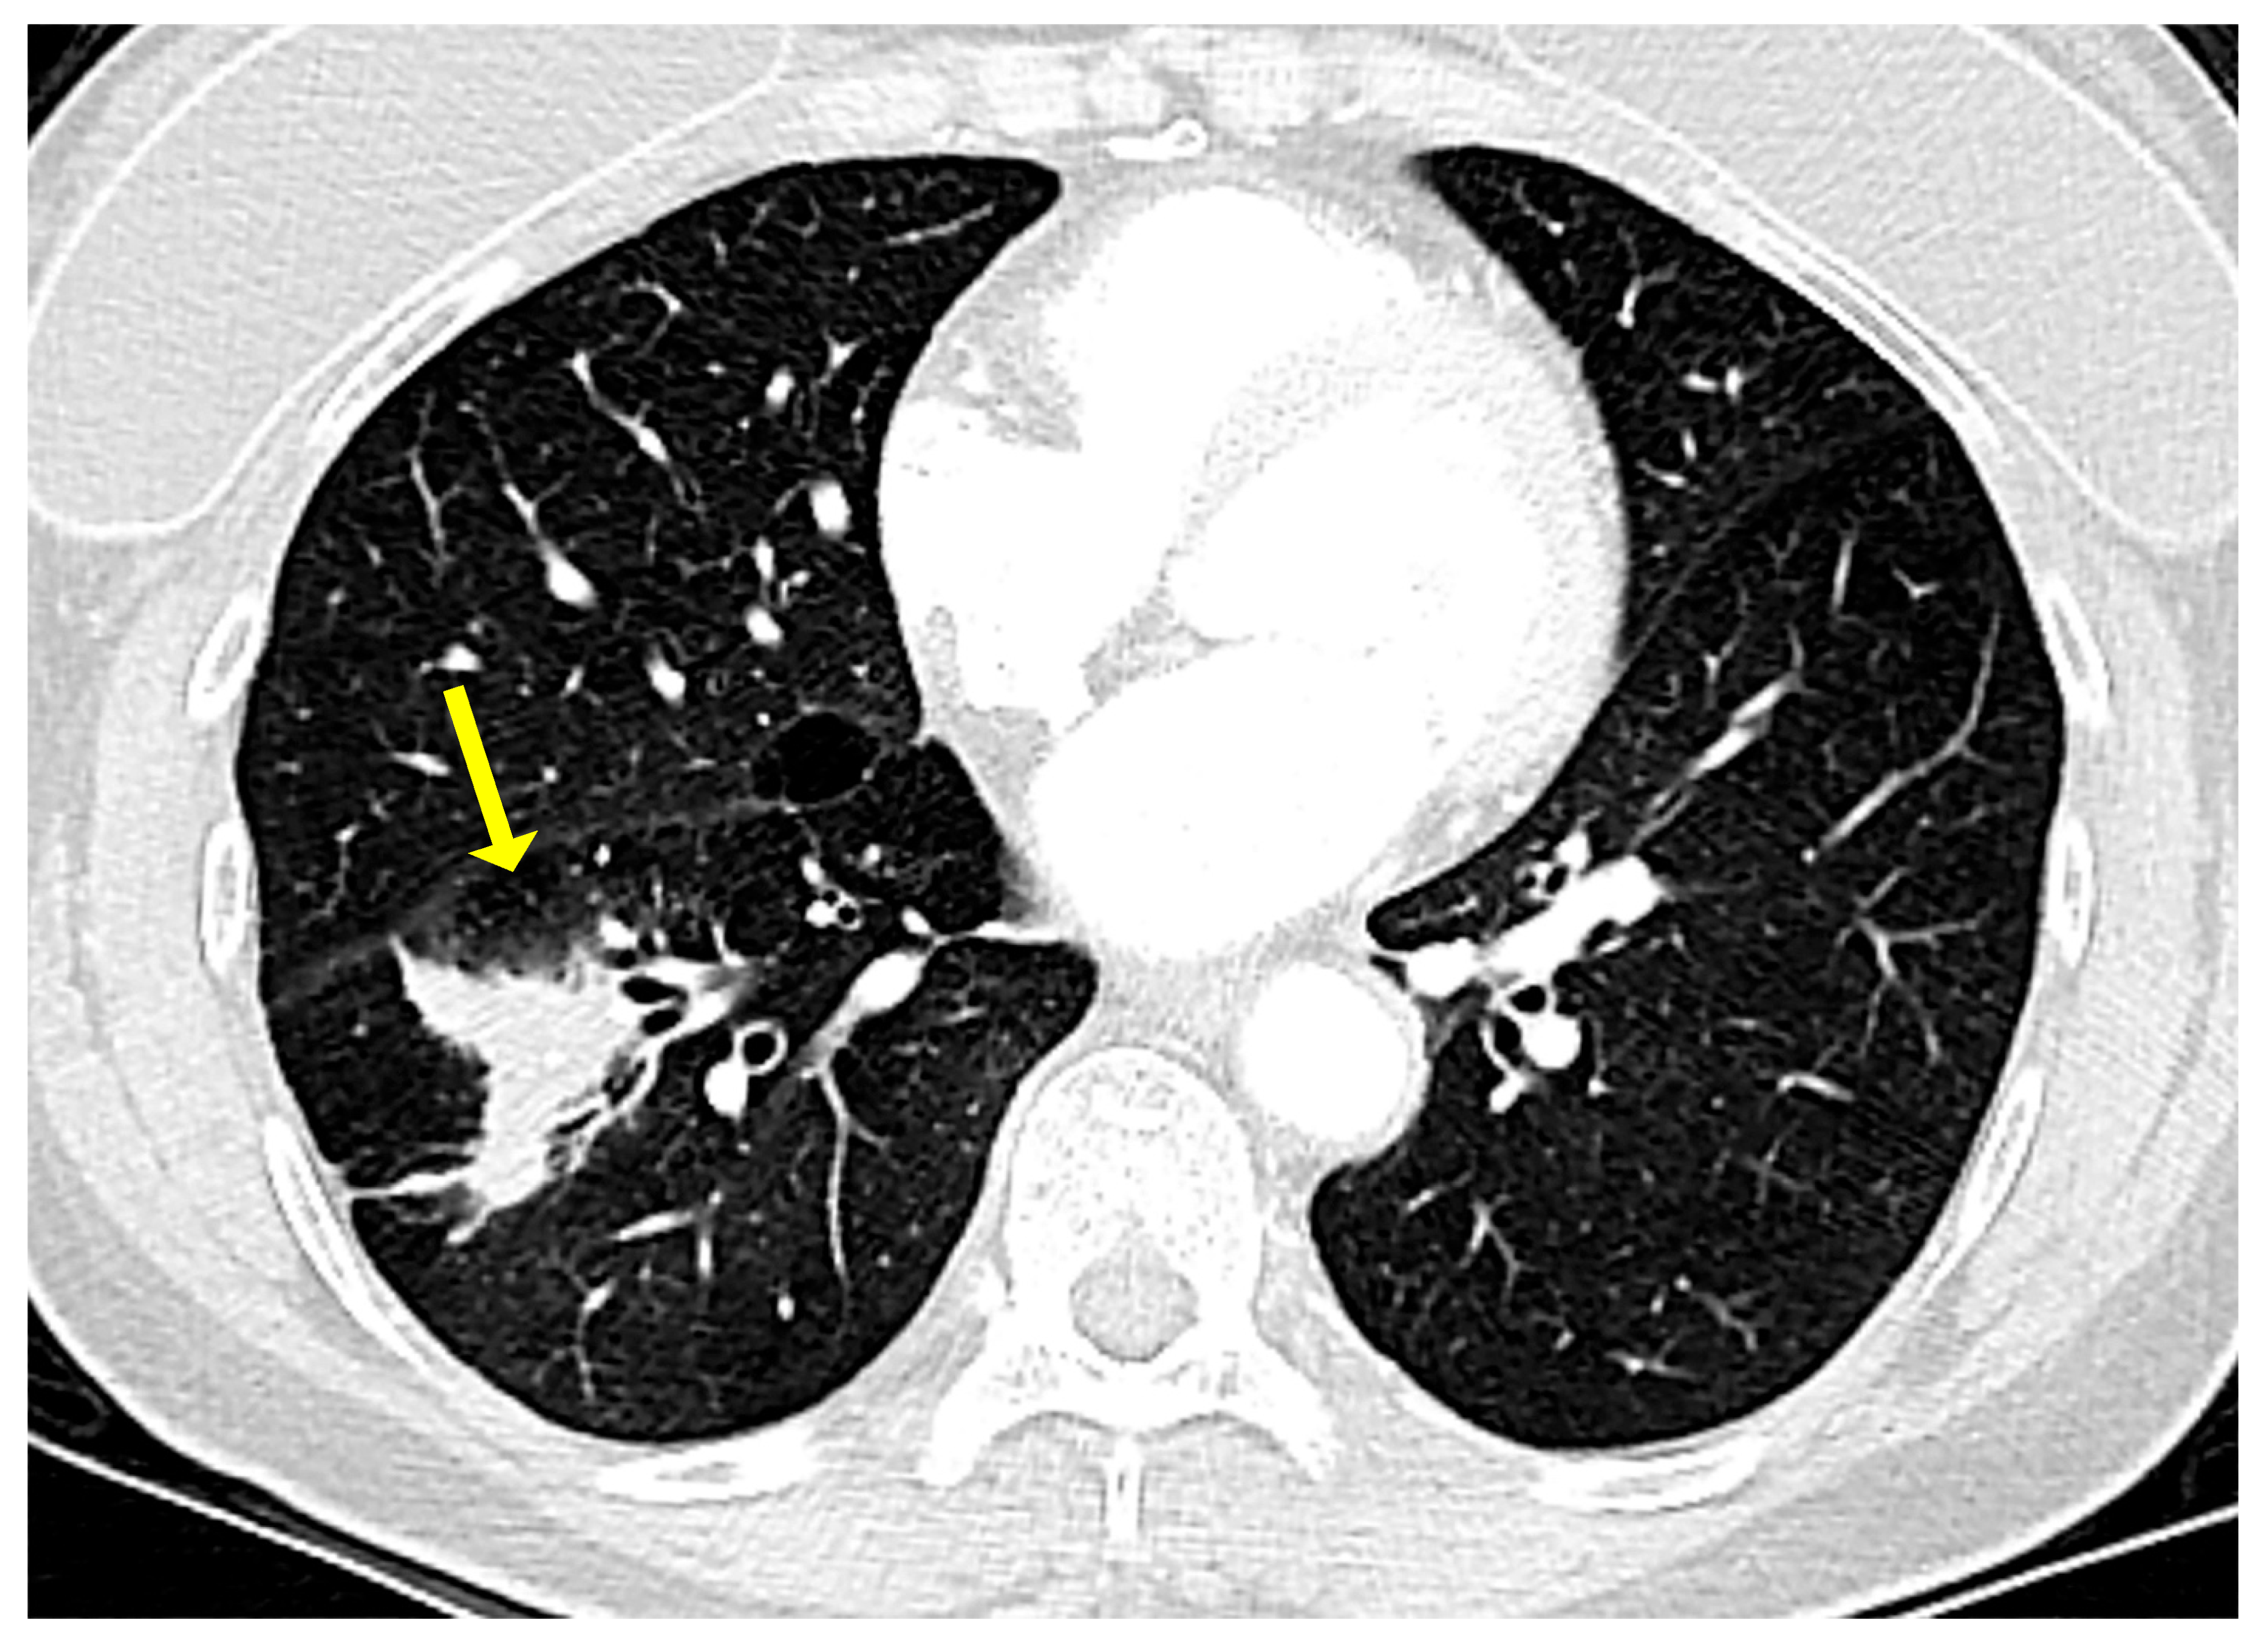

On a chest X-ray, pulmonary MALT lymphoma usually presents as a solitary lung mass. On high resolution computed tomography (CT) scan and magnetic resonance imaging (MRI), this lymphoma may present as a ground glass infiltrate with air bronchograms (Figure 1), as a peripheral mass with pleural thickening [8,9,10], or as consolidated lung parenchyma with air bronchograms and areas of apparent cavitation [11,12,13].

Figure 1.

Computed tomography in a case of pulmonary marginal zone lymphoma of mucosa-associated lymphoid tissue (MALT lymphoma). There is an ill-defined lesion in the right lower lobe originally thought to represent pneumonia (arrow). This lesion did not resolve with antibiotic therapy. Note the air bronchograms towards the medial aspect of the lesion.

Multiple or bilateral lesions, a pattern resembling LIP, or endobronchial lesions may occur but are uncommon [10,14]. Hilar or mediastinal lymphadenopathy is seen in ~30% of cases [15].